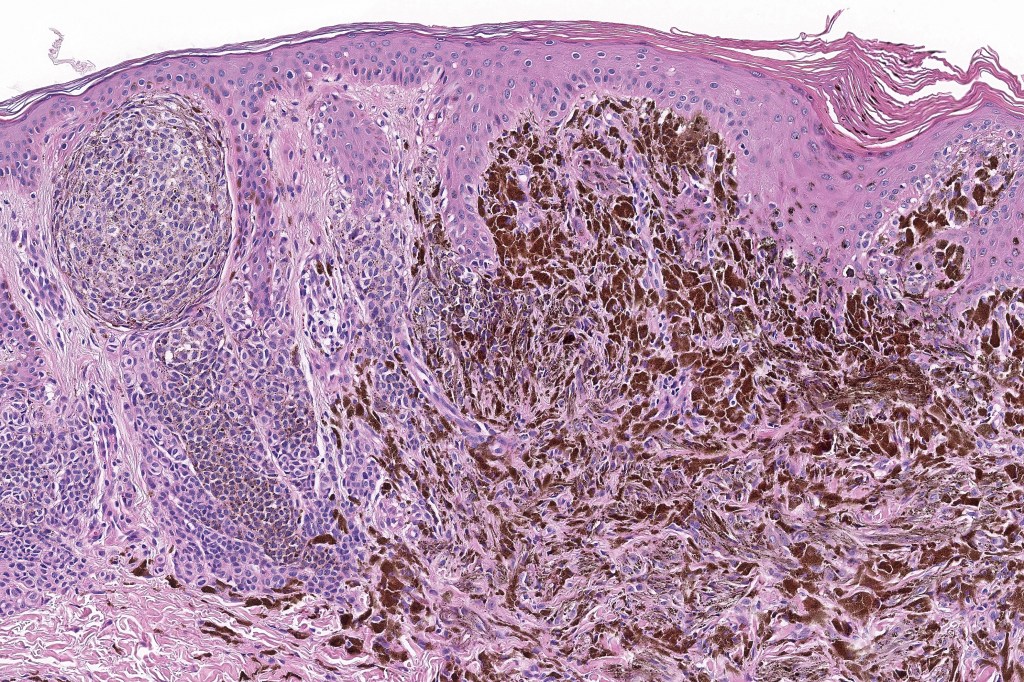

Combined congenital & blue nevus (same case as the clinical photographs coursty of Dr. Antonina Kalmykova